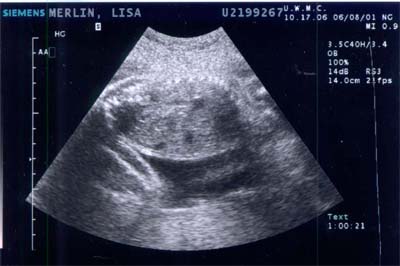

Baby A during ultrasound on 7 AUG 2001 - Week

34

The profile of the head facing left.